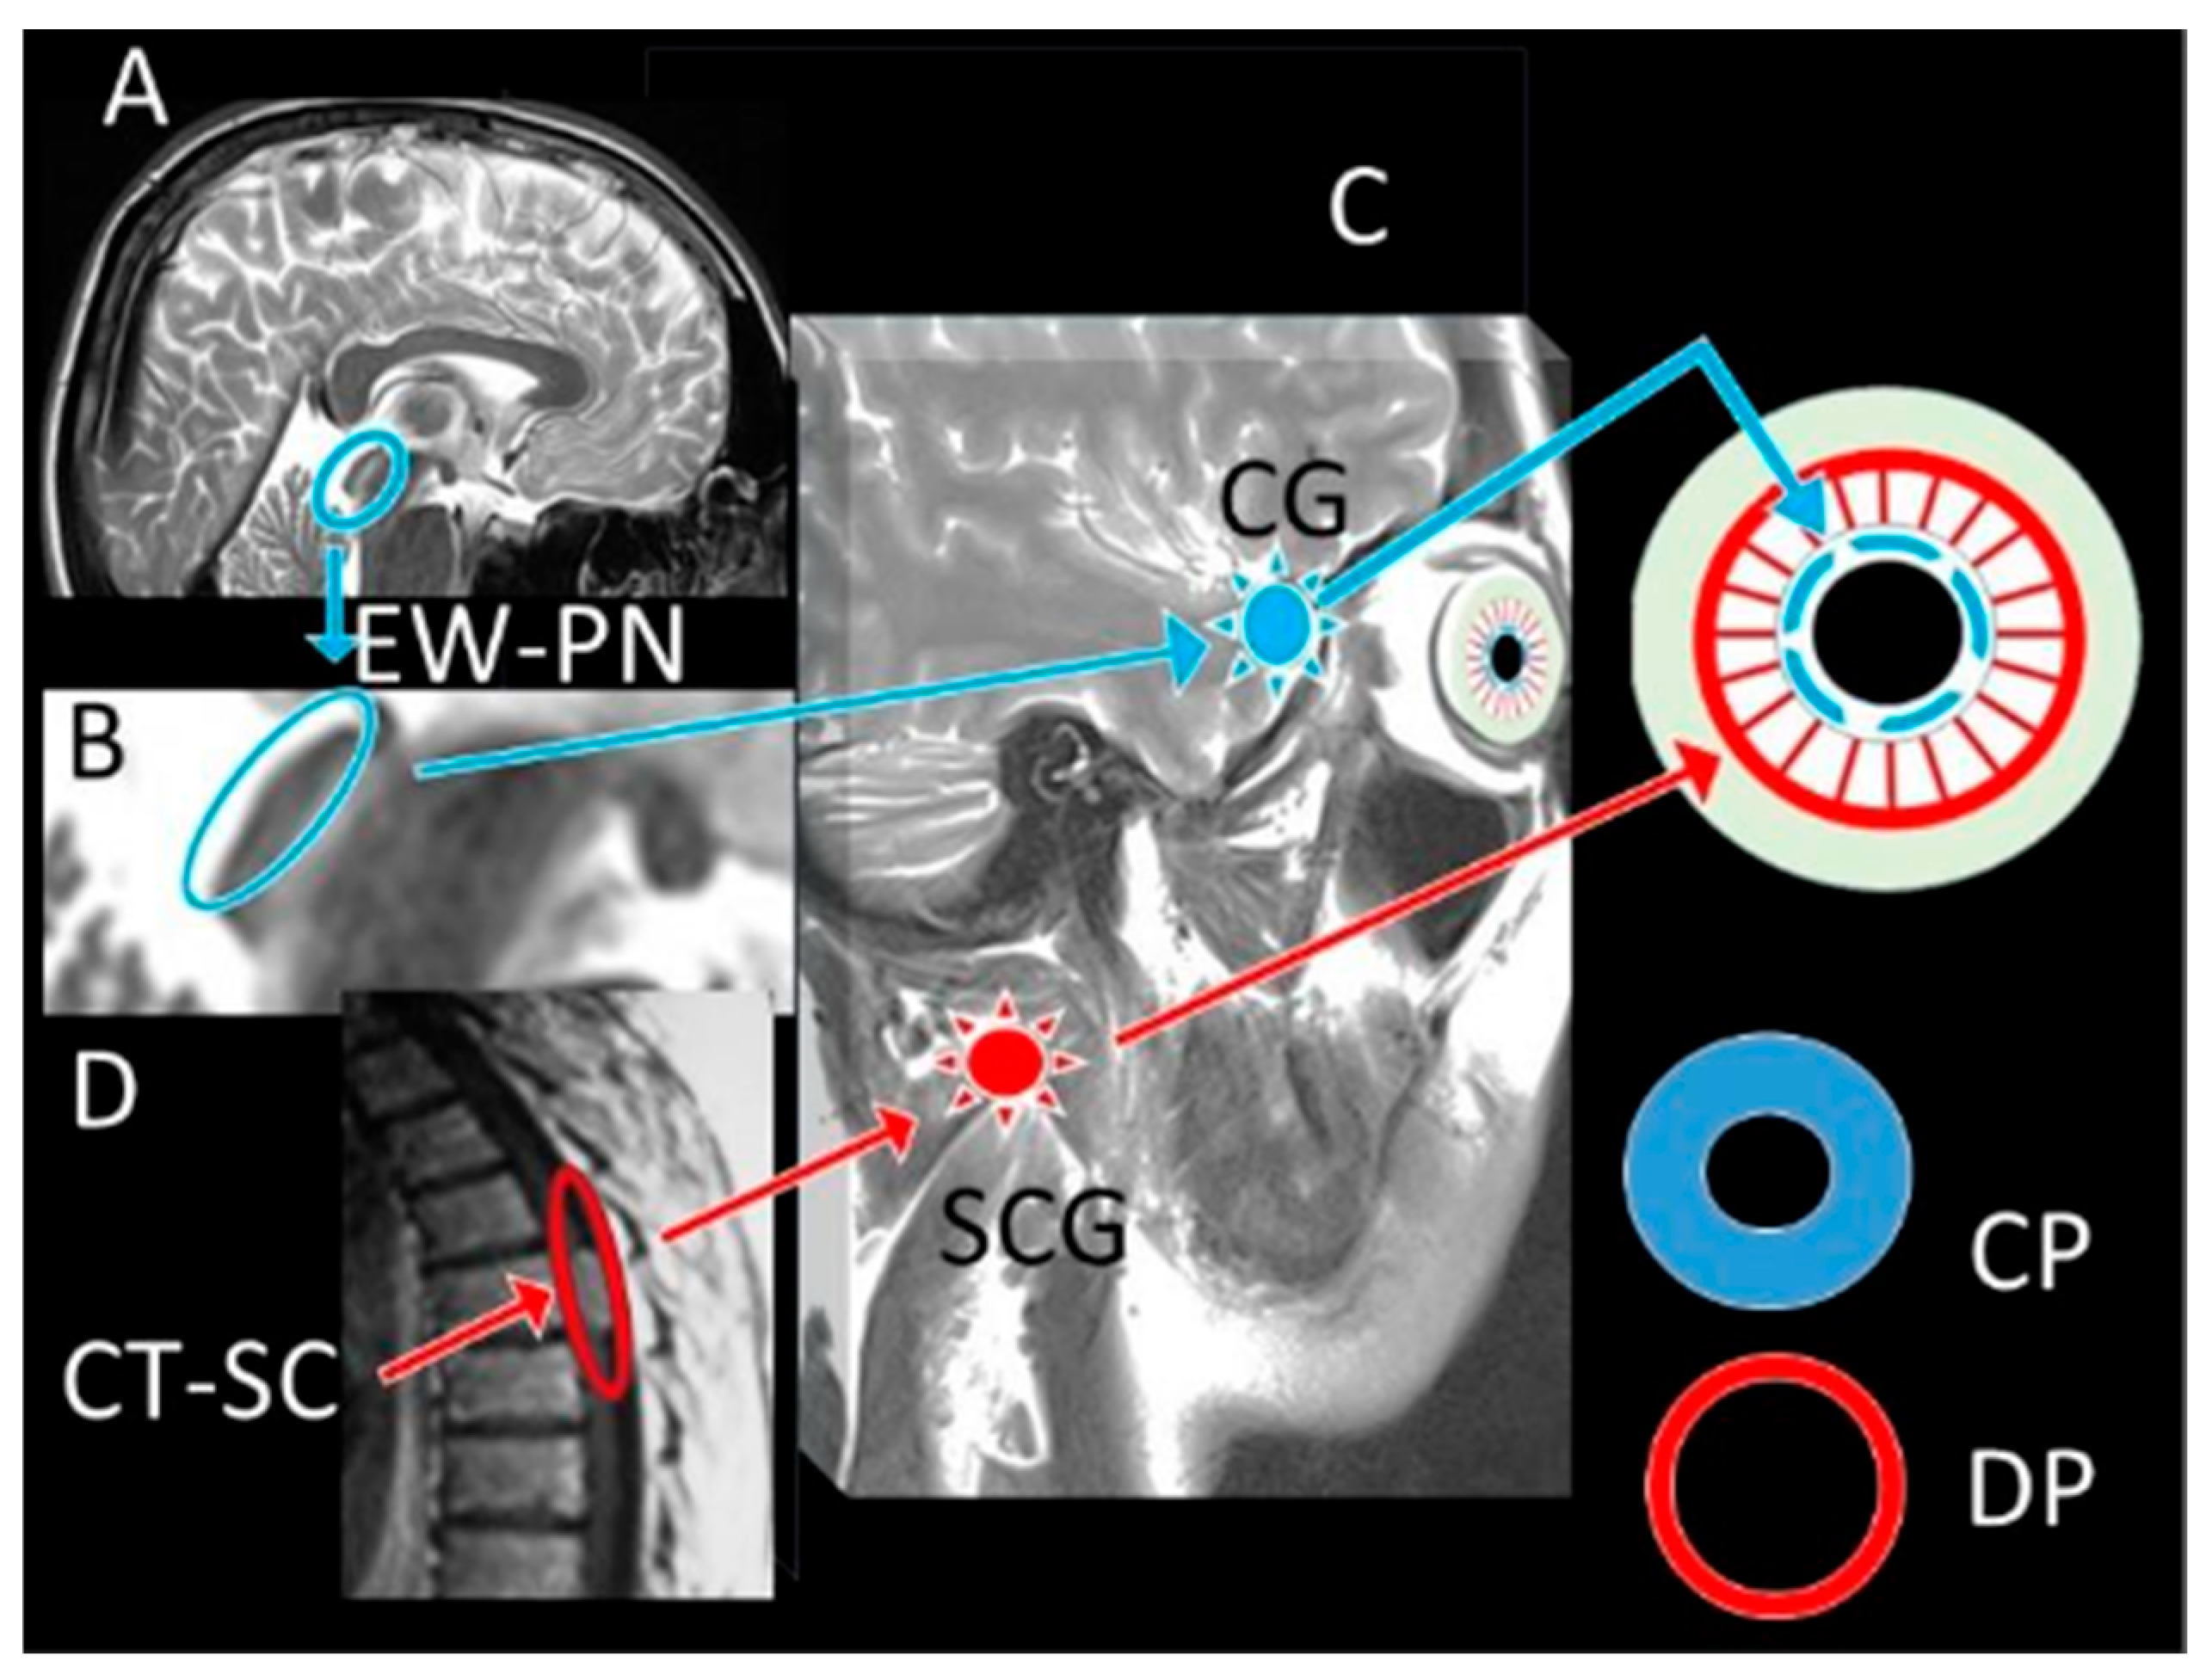

Dangerous Alarming Diameter Assessment (DADA Index) in Which the Ratio of Iris Surface/Pupil Surface Size Is More Reliable than Pupil Diameter Measurement in Comatose Patients After Subarachnoid Haemorrhage: An Experimental Rabbit Model

1. Introduction

2. Materials and Methods